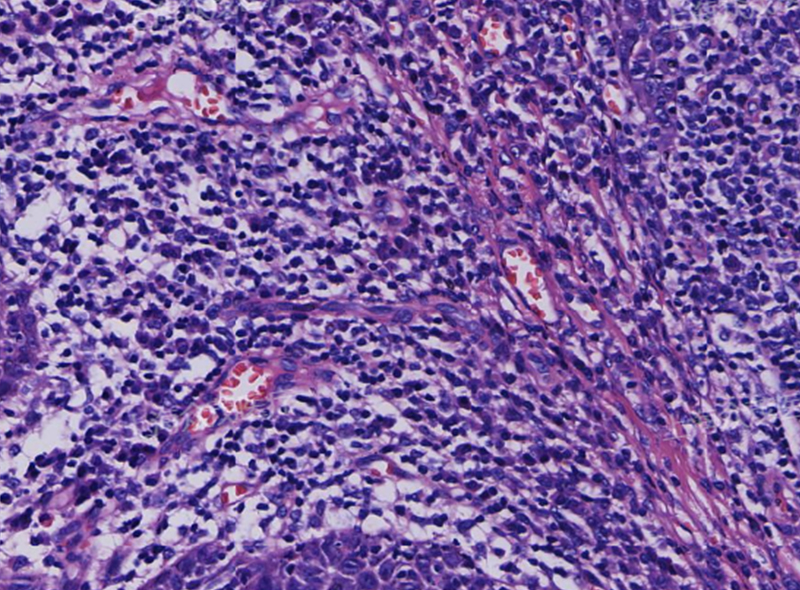

肺出血性梗死